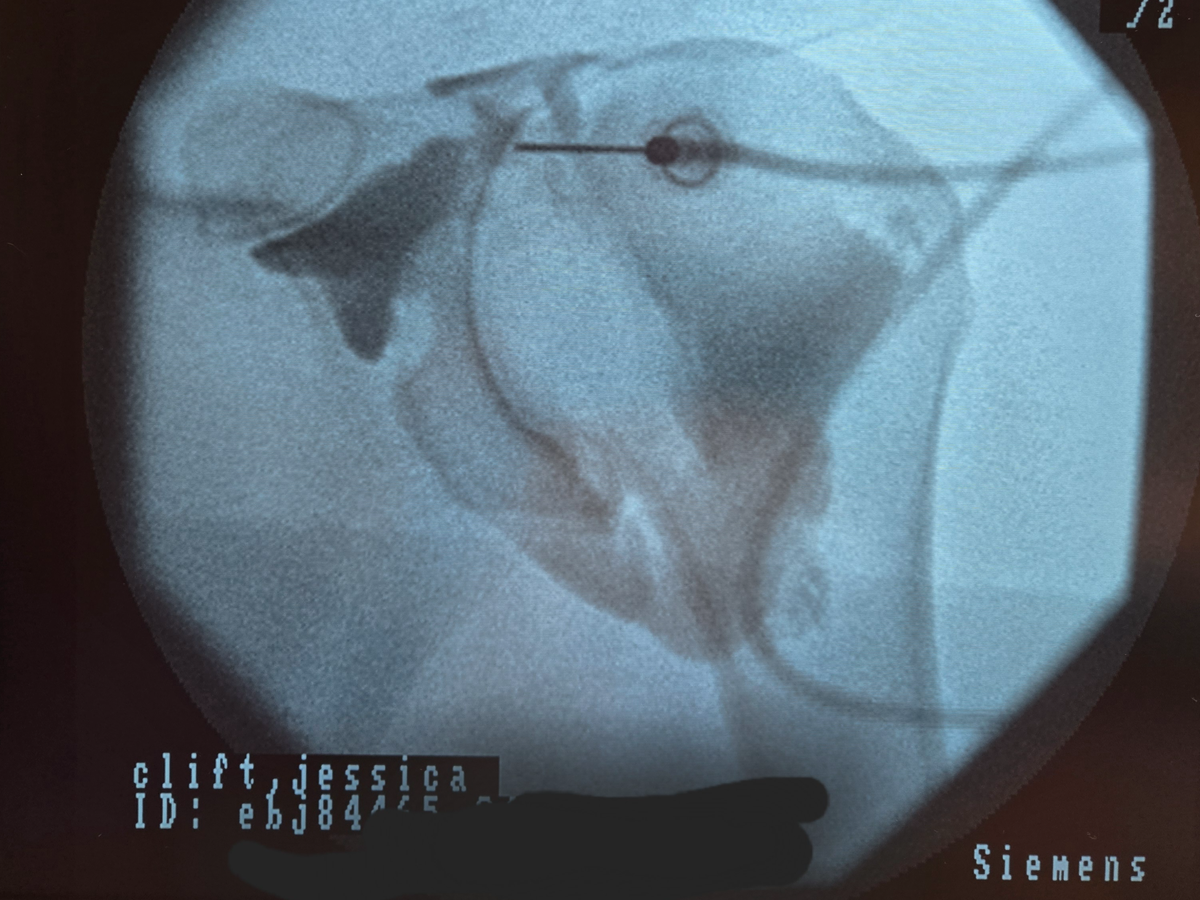

Here are the results from my MRI:

Musculature/Rotator Cuff: Partial thickness tear undersurface both supraspinatus and infraspinatus tendons, involving about 50% of the tendon thickness at the supraspinatus measuring about 1.3 cm from front to back and about 2.4 cm from side to side.

Infraspinatus shows similar high-grade partial-thickness tear involving about 75% of the tendon thickness, measuring 1.5 cm from front to back and 1.1 cm from side to side.

Subscapularis and teres minor attachments are normal. No muscular edema or fatty atrophy.

Impression:

1. Partial-thickness undersurface tear of both the supraspinatus and infraspinatus of the rotator cuff. This involves 50 and 75% of the tendon thickness.